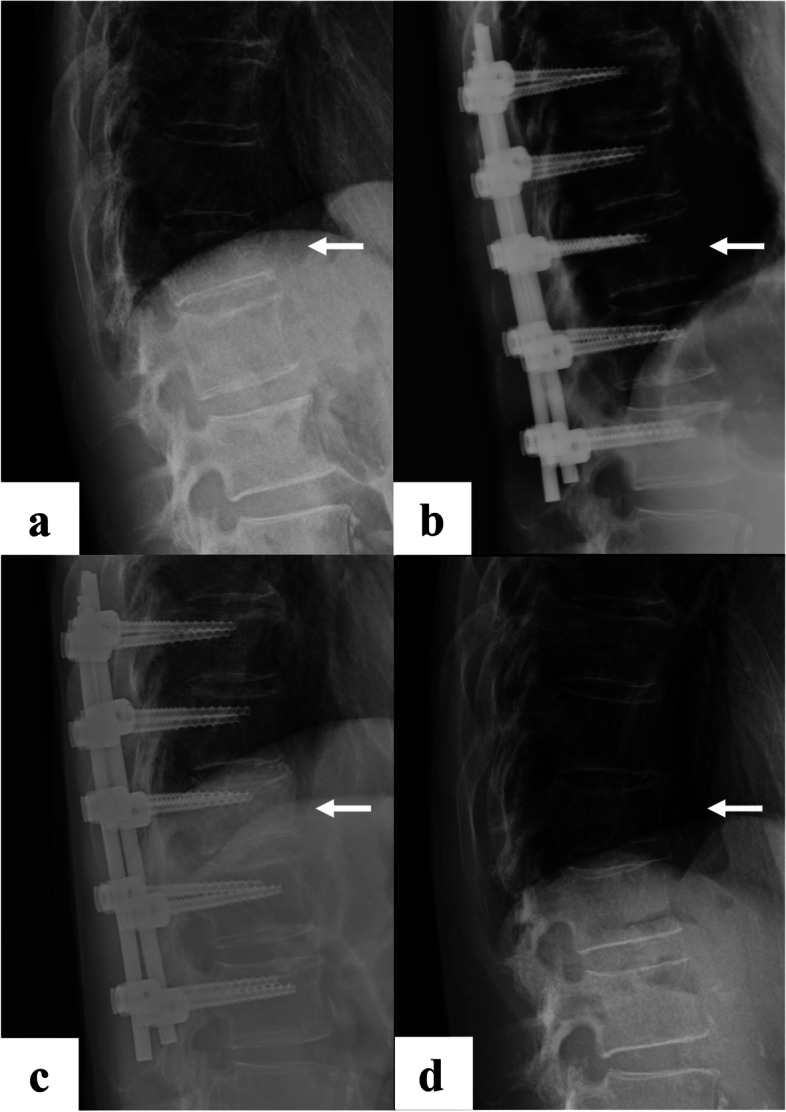

Radiographic assessment was performed using lateral thoracolumbar spine radiographs taken at four timepoints: at the time of injury, after posterior pedicle screw fixation, before implant removal, and at final observation (Fig. 1). Kyphotic angle was defined as the Cobb angle of the lower endplate line of the cranial vertebral body and the upper endplate line of the caudal vertebral body based on the fractured vertebral body (Fig. 2). The vacuum phenomenon was evaluated on sagittal CT images before implant removal (Fig. 3). All measurements were made by a board-certified orthopedic surgeon who was not involved in the patients’ care.

Fig. 1.

a: at the time of injury, b: after posterior pedicle screw fixation, c: before implant removal, and d: at final observation